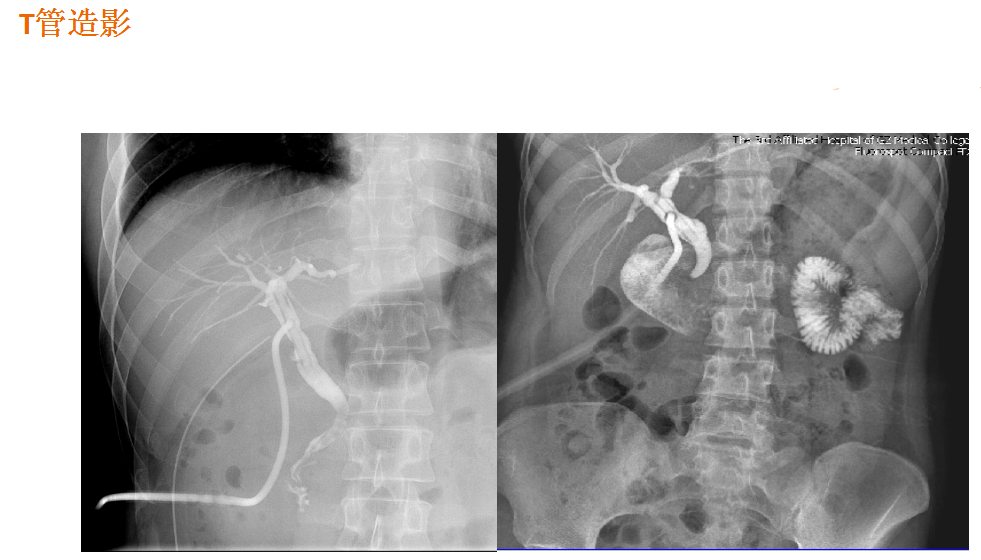

该设备属于多功能X线机,除具有传统数字胃肠机所有功能外,还有DR平板探测器X线摄影所有功能,主要用于消化道气钡双重对比造影、全脊柱拼接摄影、全下肢拼接摄影、ERCP、泌尿系造影、“T”管造影、钡剂灌肠、四肢造影、子宫输卵管造影等各类检查,是检查消化道溃疡、肿瘤、异物等疾病的主要方法之一。

在临床方面,强大的图像处理功能可以完成临床各种造影的需求。